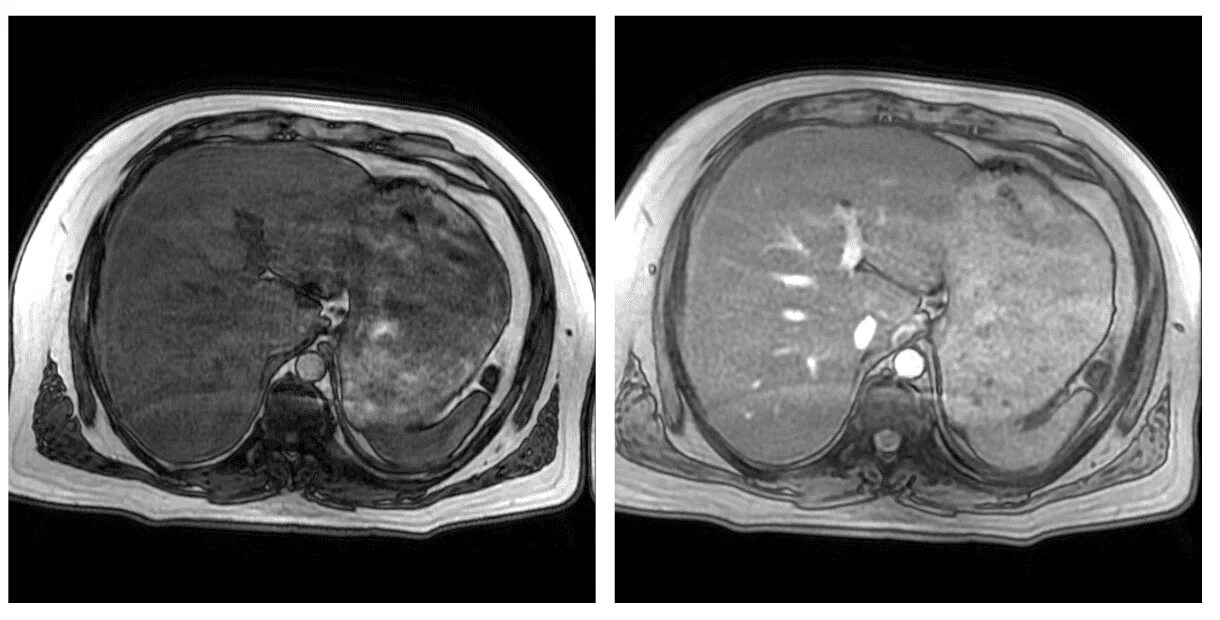

Цирроз на кт